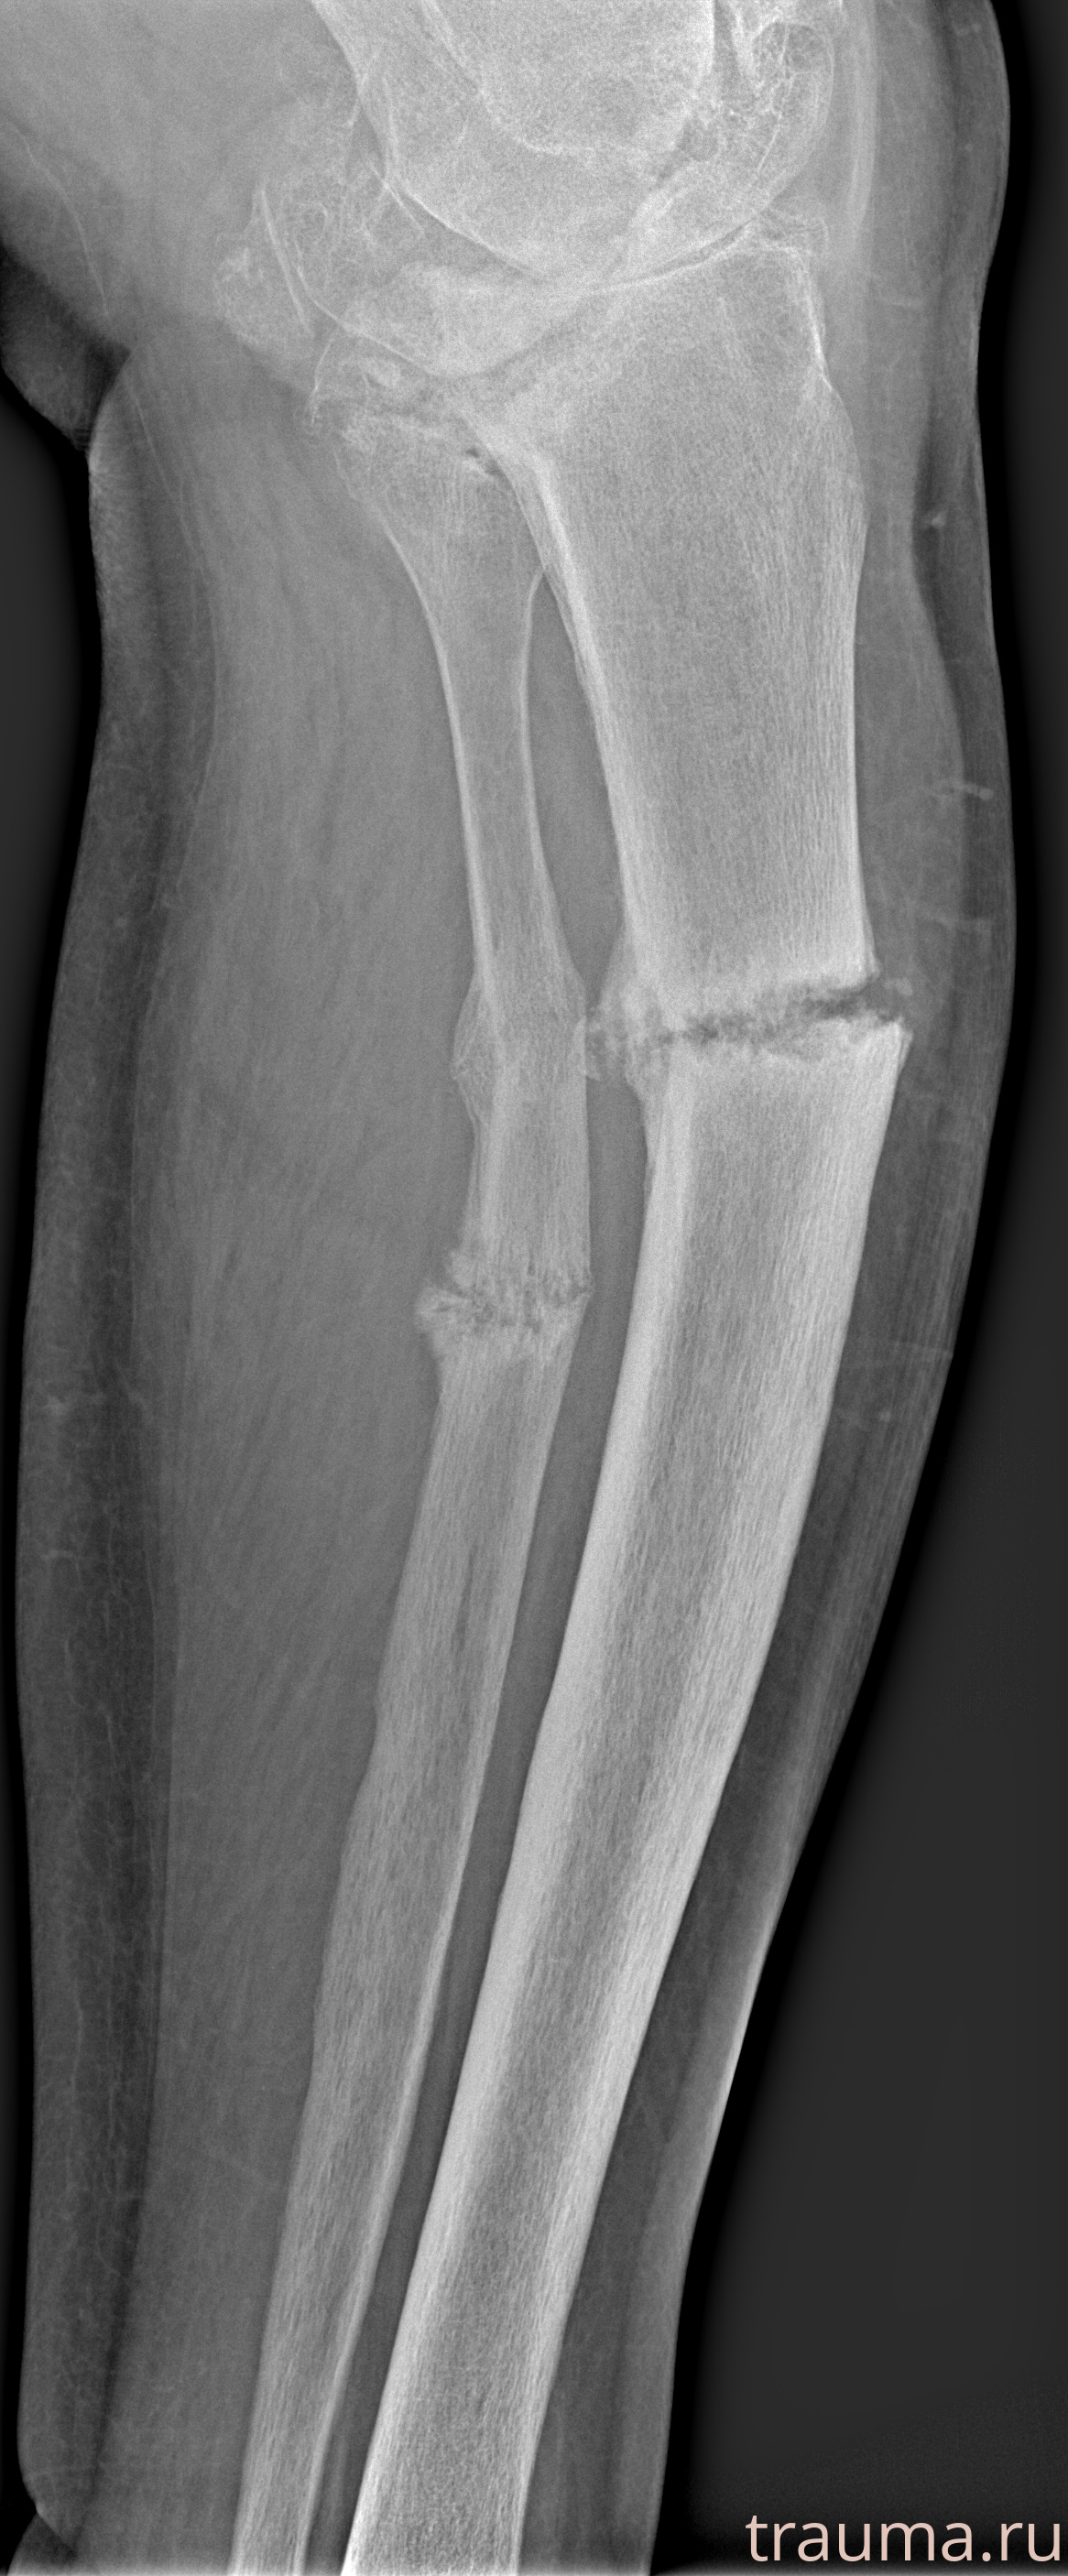

Рентгенограммы

Рентген на дому: по вашему адресу приезжает врач-рентгенолог, травматолог-ортопед с мобильным рентгеновским аппаратом, проводит диагностику травмы или заболевания, делает необходимые рентгенограммы, дает рекомендации по дальнейшему лечению. Получить качественные снимки в домашних условиях возможно благодаря уникальной методике, разработанной МосРентген Центром для института  Склифосовского